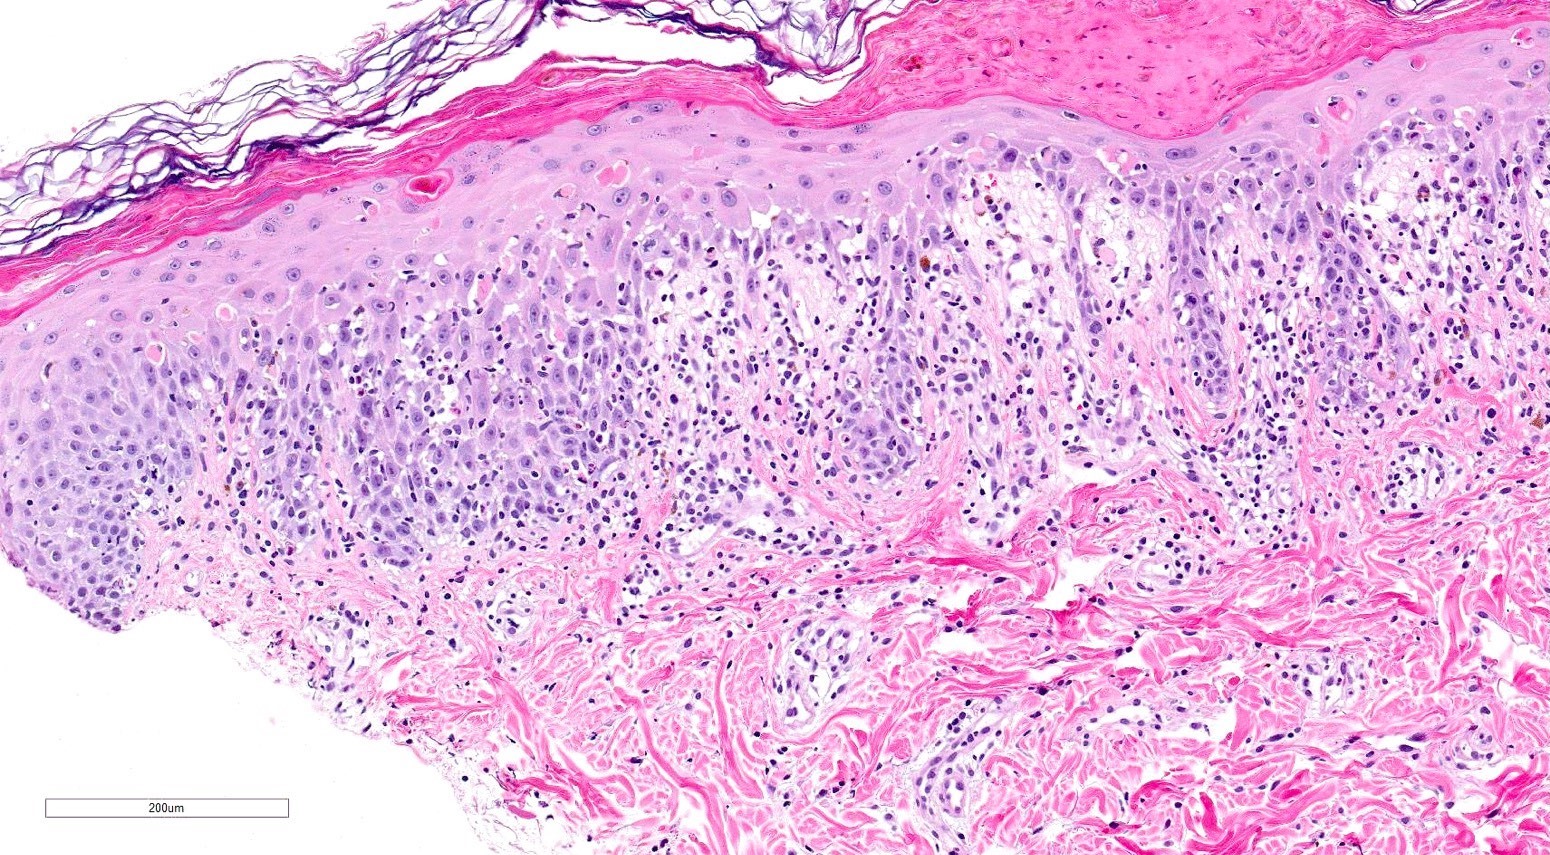

Microscopic (histologic) description

- Chronic GVHD (Biol Blood Marrow Transplant 2015;21:589, Patterson: Weedon's Skin Pathology, 4th Edition, 2015)

- Chronic lichenoid GVHD

- Acanthosis, orthohyperkeratosis, parakeratosis with hypergranulosis

- Underlying band-like lymphocytic infiltrate with basal layer vacuolization and apoptotic keratinocytes

- Periadnexal inflammation can be present

- May be difficult to distinguish from lichen planus without clinicopathologic correlation; satellite cell necrosis is the most helpful clue in GVHD biopsies to distinguish it from lichen planus

- Chronic lichenoid GVHD

Microscopic (histologic) images

Contributed by Silvija P. Gottesman, M.D. and Ohoud Aljarbou, M.D.